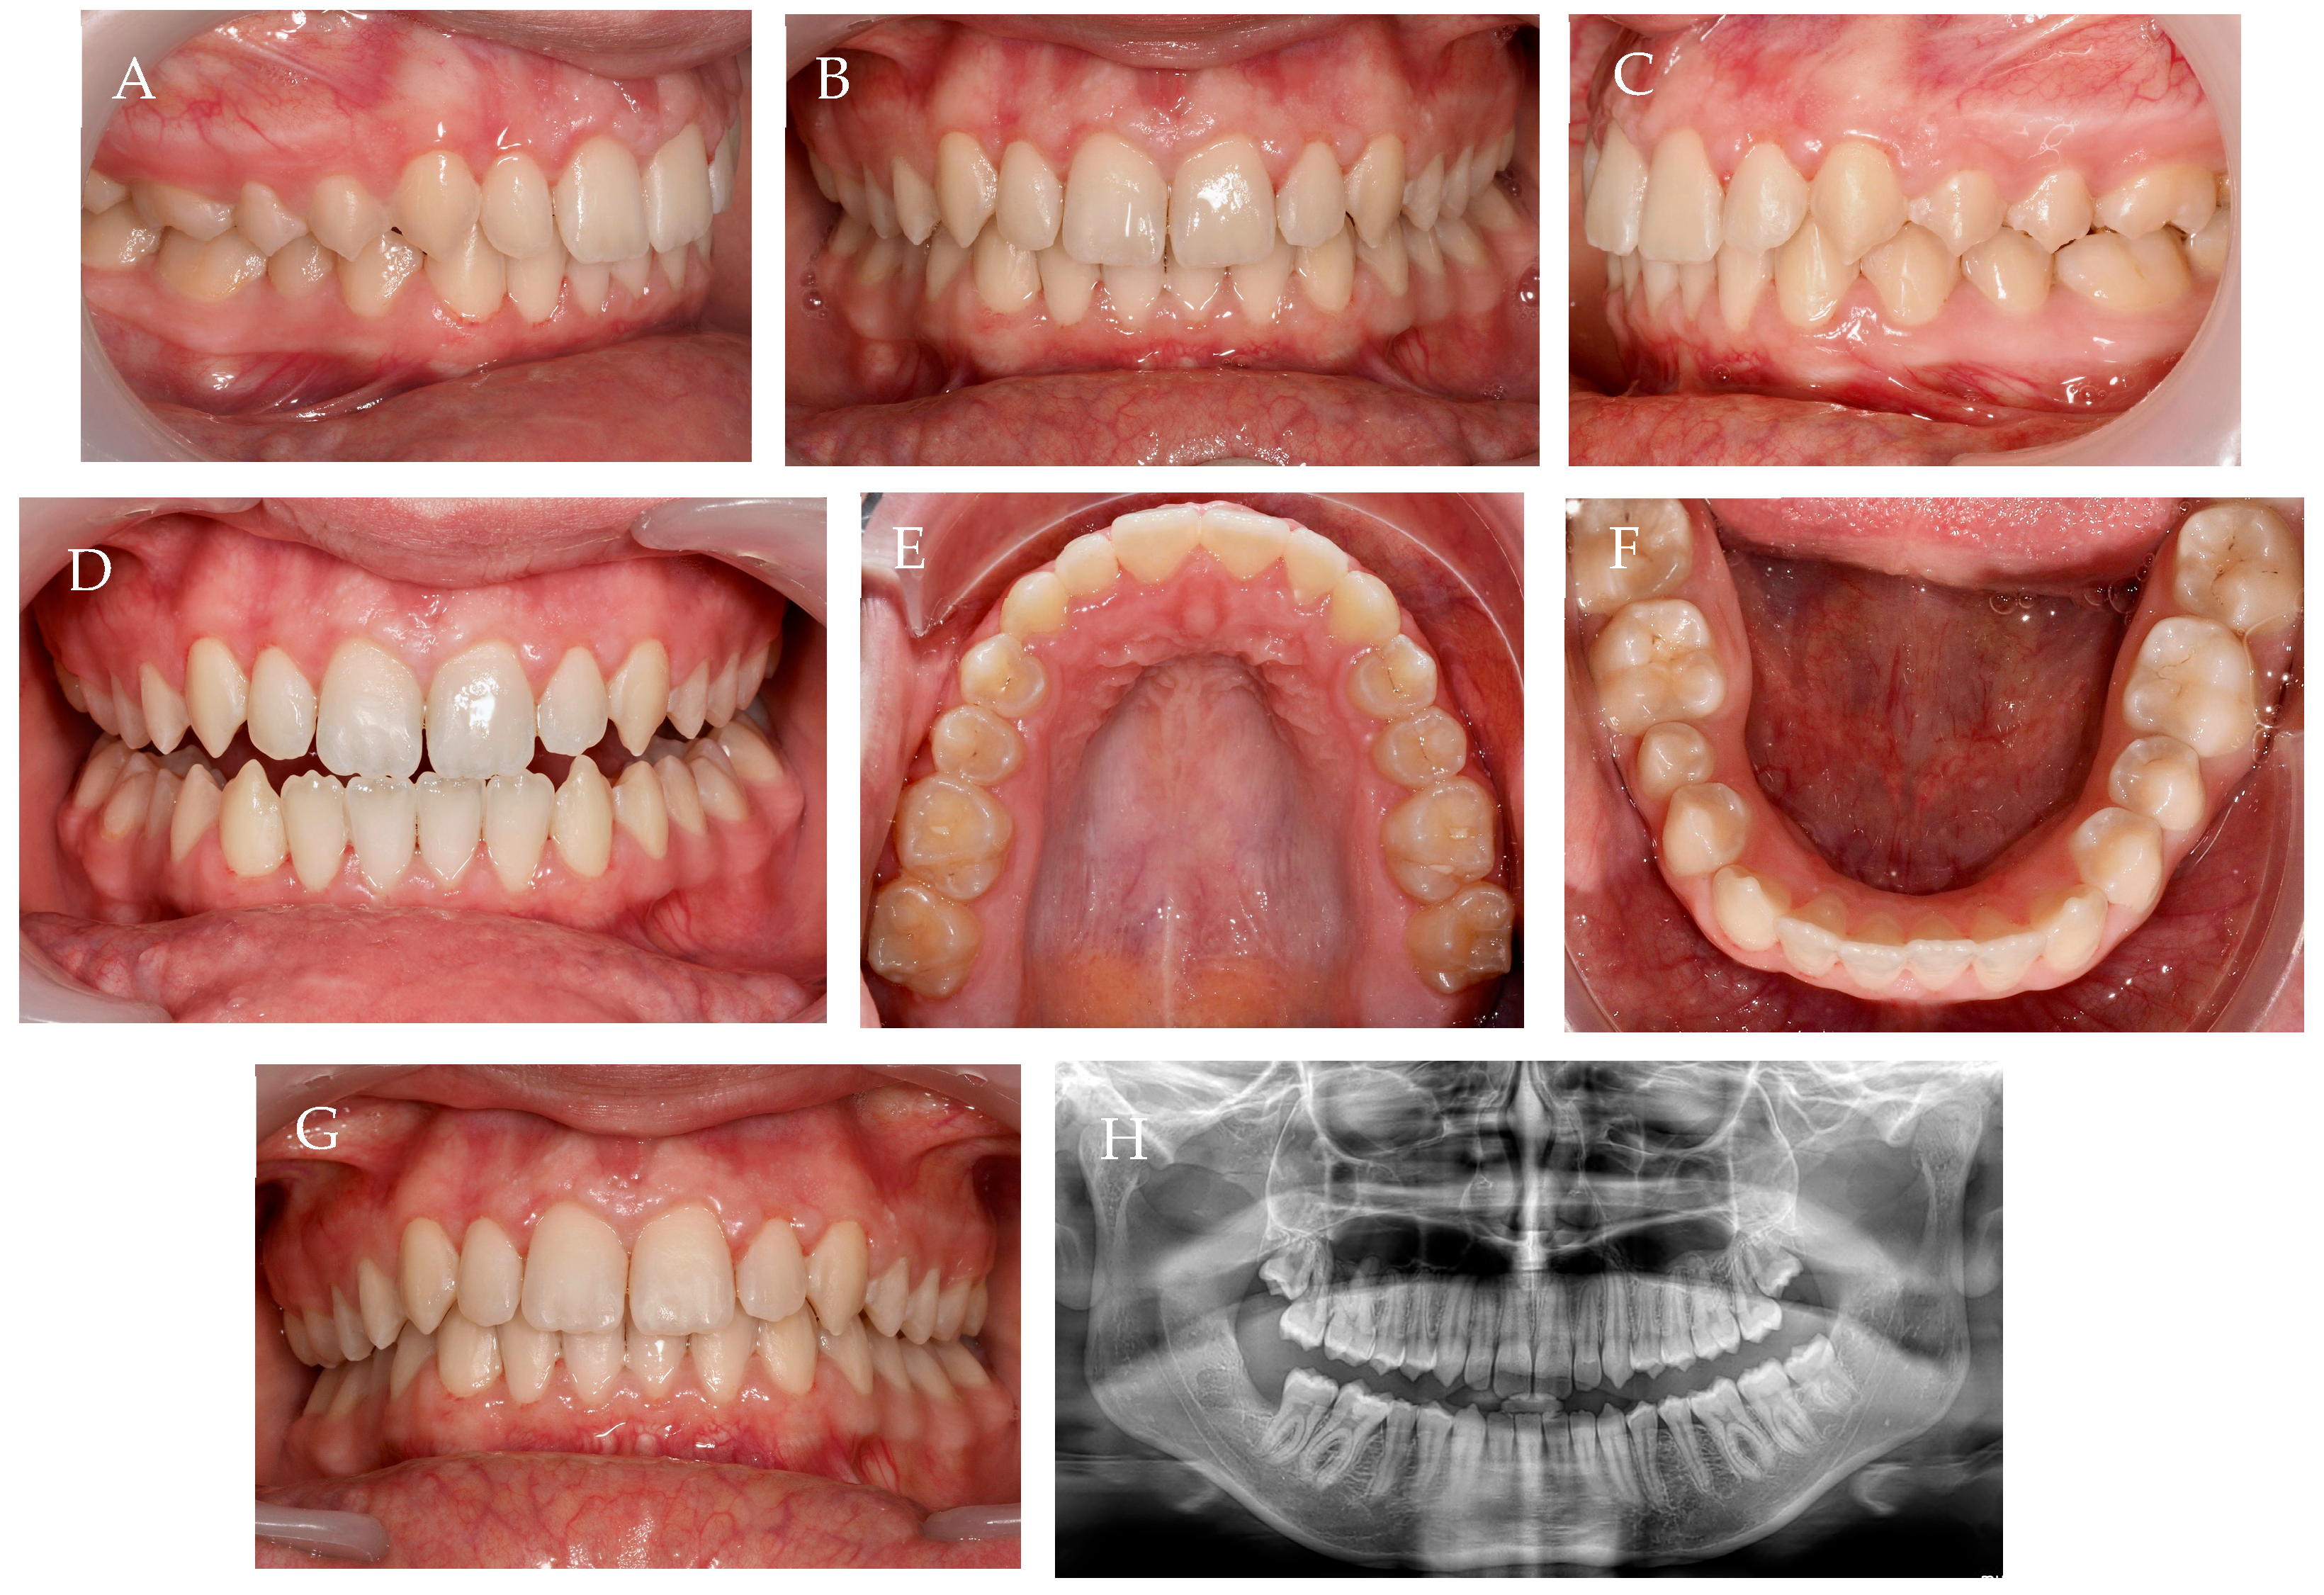

2.3. Treatment Results